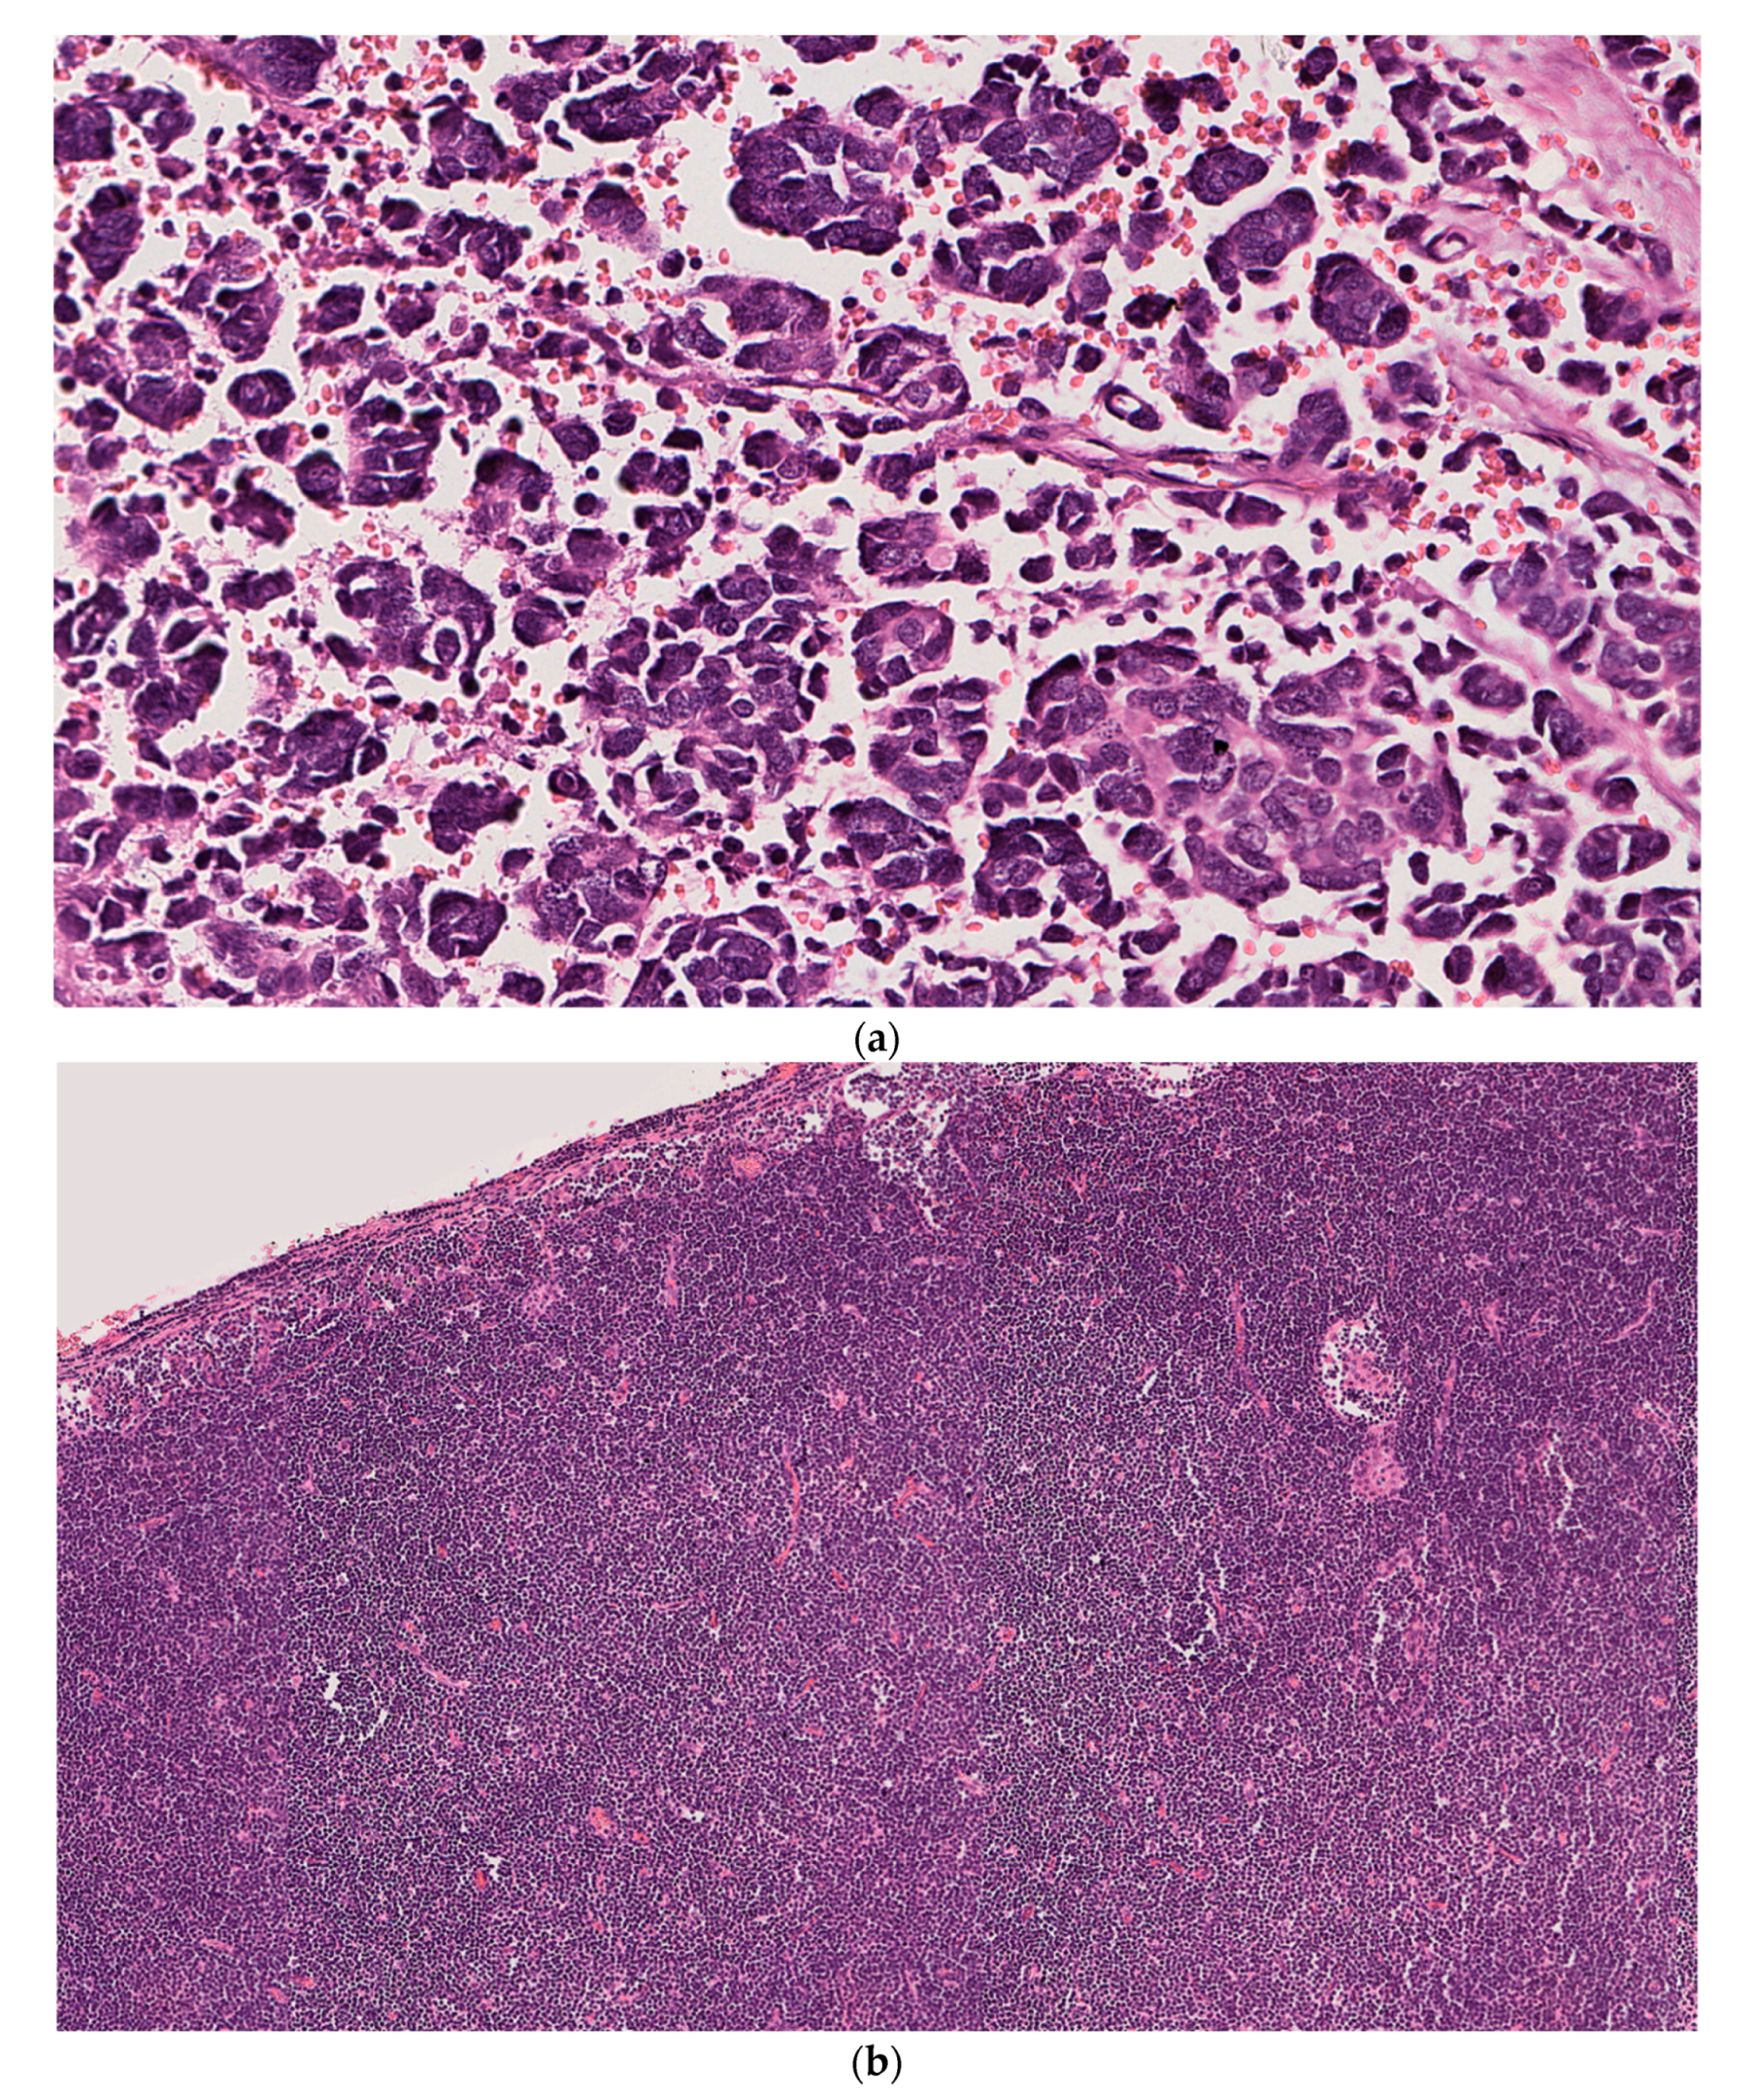

2.1. Case 1

2.2. Case 2

2.3. Case 3